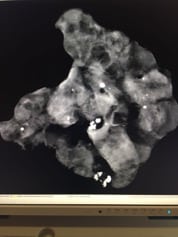

¿Cómo se ve el cáncer de mama?

• Cáncer de mama por mamografía

• Cáncer de mama por ultrasonido

• Cáncer de mama por resonancia magnética

• Biopsia de mama